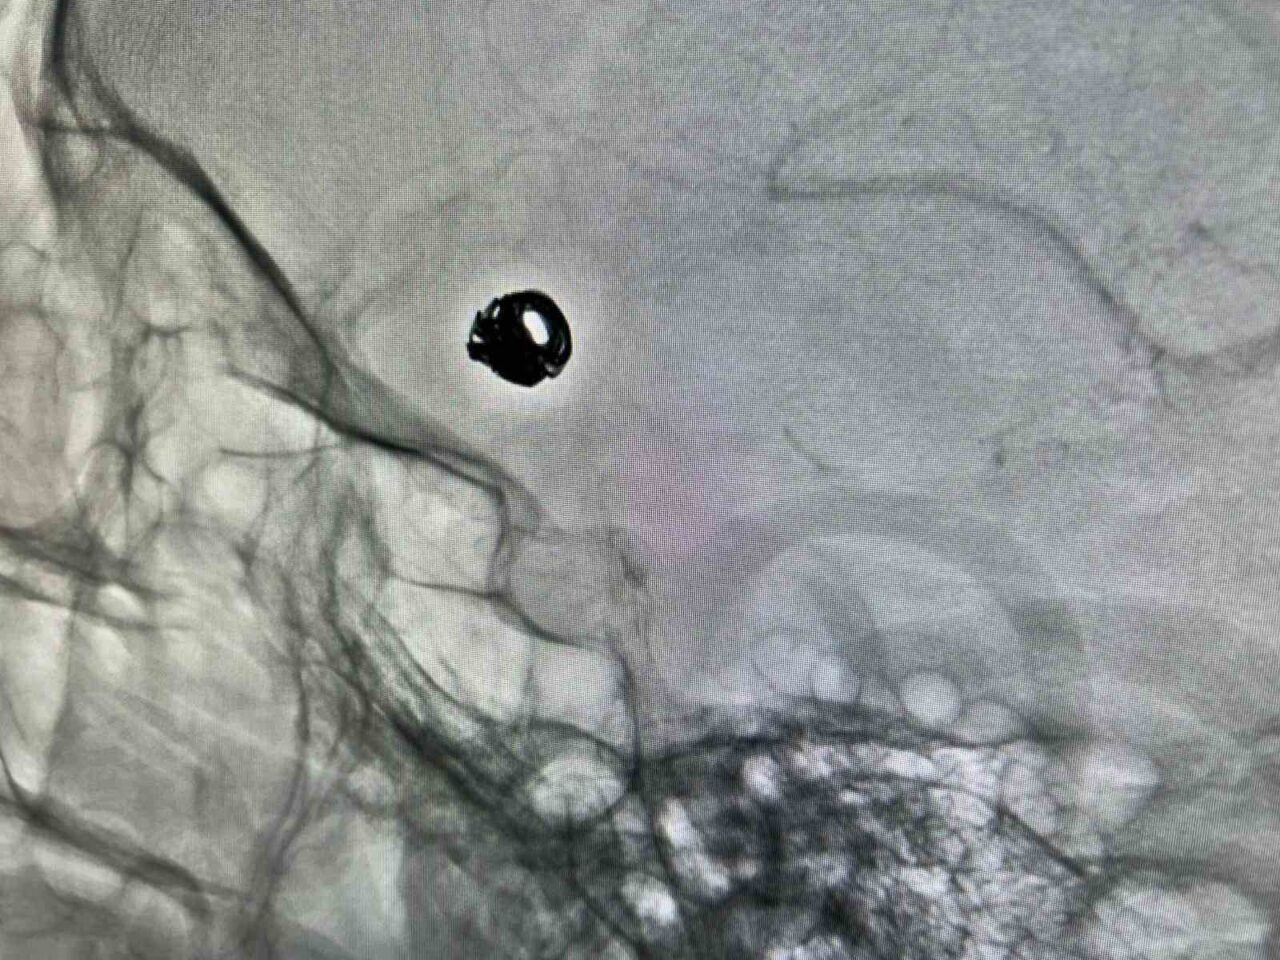

VAN EĞİTİM VE ARAŞTIRMA HASTANESİ GİRİŞİMSEL RADYOLOJİ MERKEZİ’NDE BEYİN DAMARLARINDA BALONCUK (ANEVRİZMA) BULUNAN VE BUNA BAĞLI BEYİN KANAMASI GEÇİREN 44 YAŞINDAKİ KADIN HASTA, KAPALI YÖNTEMLE YAPILAN ANJİYOGRAFİ SAYESİNDE AMELİYATSIZ TEDAVİ EDİLDİ.